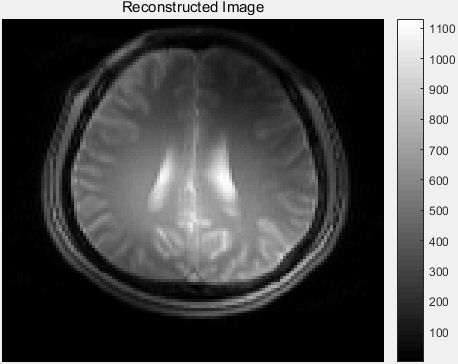

显示 RSOS 重建 MR 图像:

%recon = ifft2(ifftshift(ifftshift(grappaKspace, 2), 1)); 源代码

recon = ifftshift(ifft2(fftshift(grappaKspace))); % 120×128×5 complex double 修正

reconImage = rsos(recon); % 120×128 double RSOS 组合重建结果

汇总对比显示:

figure;

imagesc(originalImage);

title('Original Image');

subplot(2, 2, 2);

imagesc(dsImage);

subplot(2, 2, 3);

imagesc(reconImage);

subplot(2, 2, 4);

imagesc(deltaImage);